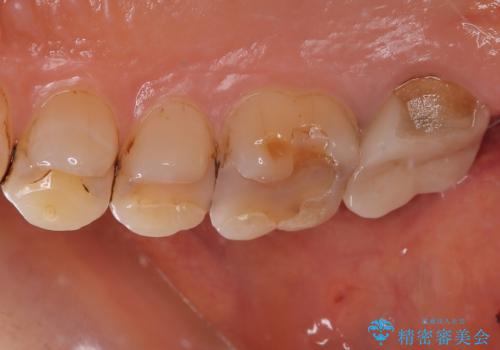

拡大鏡視野下で古い被せものを除去し、オールセラミッククラウンに適した形に整えました。

歯と歯茎の間に圧排糸と言われる糸を入れてシリコーン印象材にて型どりをしました。